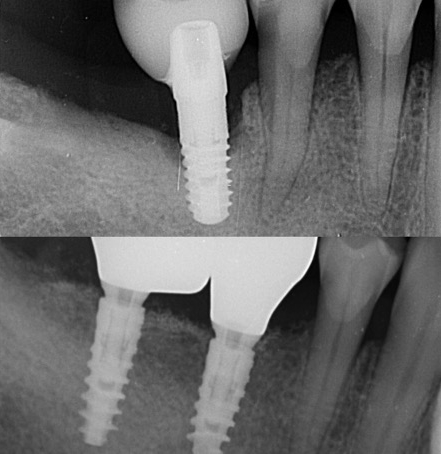

En effet, une reconstruction osseuse (Greffe osseuse) est indispensable, pour rétablir la hauteur ou la largeur de l’os maxillaire, avant ou en même temps que l’implantation. Ce sont soit les os du patient ou un substitut osseux qui sont utilisés comme matériau de comblement.

Les études nous montrent des résultats extraordinaires avec l’utilisation exclusive ou mélangée que ce soit avec de l’os synthétique ou de l’os autologue (os prélevé dans la bouche du patient pendant l’intervention de reconstruction osseuse).

Il y a plusieurs techniques des reconstructions osseuses et une planification correcte nous donne la possibilité de choisir la technique la plus appropriée pour chaque situation.